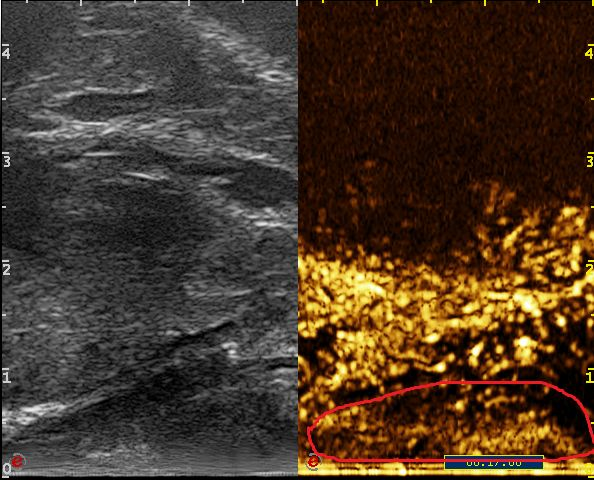

Elasticity imaging: 弹性成像

Freehand elasticity imaging: 徒手弹性成像(FEI)

基于应力的弹性应变成像,提供组织软、硬病变的诊断信息

• 徒手弹性成像是通过移动探头对检测部位进行挤压使组织产生运动,并利用回 波信号进行运动检测得到表征组织弹性的应变图像

• 业界最高帧率 50fps vs 20fps

• 业界最大检测区域—全器官检测

Acoustic Radiation Force Imaging: 声辐射力弹性成像(ARFI)

基于声能 (ARFI)和剪切波波速的实时弹性成像,提供组织软、硬病变的定量评价。 通过自动发射一定能量的声波通过声辐射力直接对所需要检测部位进行激励,用 于激励的声波犹如无形的手直接去推动组织产生运动,从而得到表征组织弹性的图像,这种新兴弹性成像技术可以得到更精确的组织应变图像

shear wave imaging:剪切波成像技术(SWI)

基于ARFI技术衍生的超声剪切波成像,通过调整脉冲激励方式,根据水平方向多个点的位移-时间曲线估算横向传播的剪切波波速,然后利用剪切波传播特性与生物组织弹性特征之间的内在联系,最终定量重构组织的弹性模量以形成二维的图像。